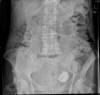

Dilatación colónica. Diverticulosis.